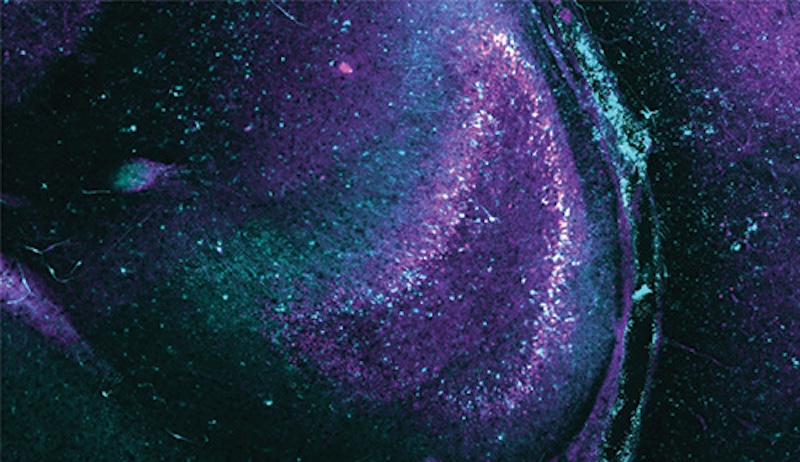

The researchers delivered genes for light-sensitive proteins to hippocampal slices, seen here, to observe seizure-like neuron activity. Credit: UC Santa Cruz/Nature Neuroscience.